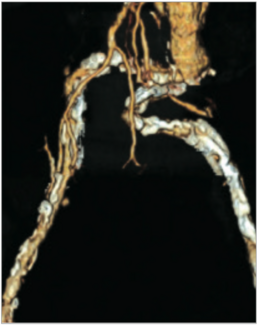

We suggest approaching the important topic of alternative arterial access with the following questions: 1) WHAT is it?; 2) WHY is it needed?; 3) WHERE are the access sites?; 4) HOW safe is it?